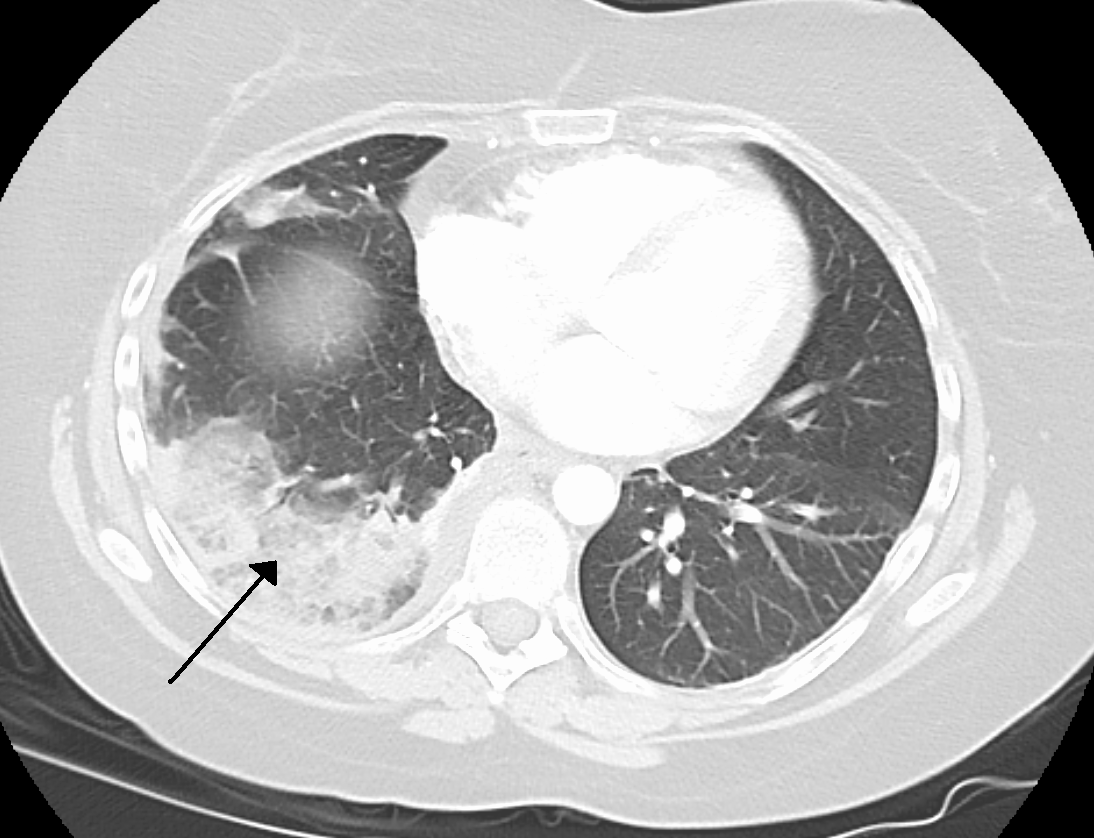

In March of 2026 I had the terrifying experience of having a Pulmonary Embolism. Two actually, accompanied by two infarcts (lung tissue death) with one in each lung. Oh, and a pleural effusion for good measure. I was transferred (almost airlifted) to a Level II trauma center where I spent two days in the ICU and two more in a regular room. It was a rough few days.

Please note that the CT scan picture above showing a pulmonary infarct (black arrow) is not of my lung, but is rather the pic from the Wikipedia article on Lung Infarction. That article has some gross autopsy photos in it, so if you’re squeamish about such things, consider not clicking the link. Also, some of the first few dates mentioned may seem unimportant, but bear with me because I believe they were.

Luckily, a short while later (which felt like 12 hours) the head ER doctor and the wonderful nurse came in to calmly and rationally explain everything to us. I had massive Deep-Vein Thrombosis (DVT) in my right leg, the clots had separated and lodged in each of my lungs (bilateral pulmonary emboli), each of which causing infarction (tissue death). In short, the pain was due to parts of my lungs dying. Neat. <cough> (ow). Oh, I also had Pleural Effusion when means fluid between my lungs and the tissue that surrounds them because I guess the other stuff wasn’t exciting enough for a Monday morning. We made sure to complain about the previous doctor’s utter lack of compassion and bedside manner, a complaint about which they did not seem surprised.

Word-nerd aside: the scans showed two infarcts. An infarction is the process of tissue death, while an infarct is the actual area of dead tissue caused by blood loss. An infarction is rarely visible on scans unless it happens during something like a PET scan, while an infarct is visible after the fact on CT scans because it’s basically a scar.